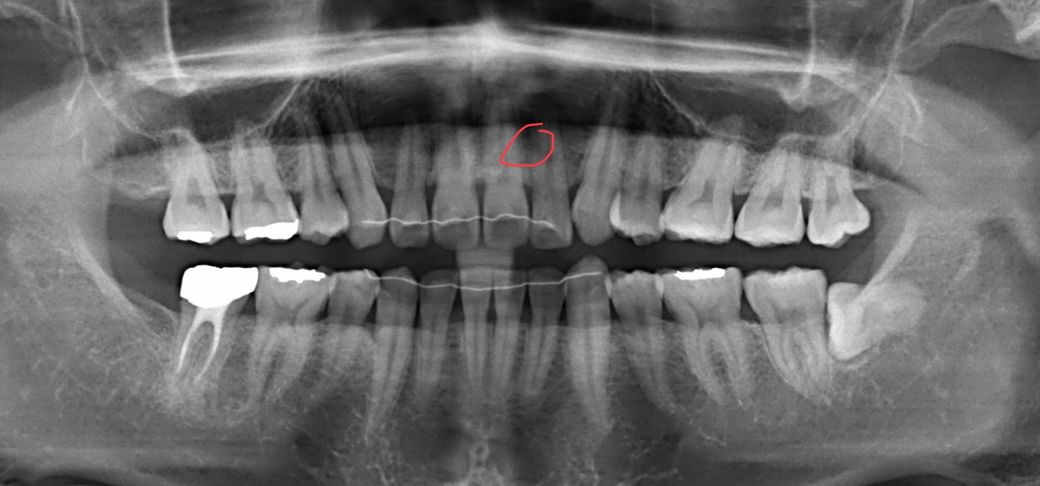

정중과잉치 발치 후 앞니가 예민합니다

23년 5월 말에 정중과잉치를 발치했는데요.

빨간색 동그라미 부분입니다

그런데 빼고 난 이후에 앞니가 감각이 달라졌습니다.

뭔가 빠질것 같고, 약해진듯한 기분이 듭니다.

입천장 쪽으로 발치를 했는데 그쪽에 아직까지 잇몸뼈가 생성이 안된 걸까요?

12월에 발치 치과에 내원했는데 엑스레이를 찍어보더니 괜찮다고 합니다.

뒤쪽 잇몸뼈 생성은 ct를 찍어봐야 정확하게 알 수 있지 않나요??

해당 사진만으로는 큰 이상한 부분을 찾아내기는 힘듭니다. 현재와 같은 느낌이 계속 든다면 dental-ct 등을 찍어보는 것이 필요할 수 있습니다. 지속적으로 해당 불편감이 있다면 ct 촬영을 권해드립니다.

과잉치를 발치하고 나면 해당부위가 비어있기때문에 약한 느낌이 들수 있습니다.

엑스레이 촬영 시 문제가 없다면 아직 뼈가 덜 차올라서 그럴 가능성이 높습니다. 지켜보시는 게 좋겠습니다.

정확하게 확인을 하기위해서는 CT를 찍어봐야 알수 잇을것같습니다. 과잉치를 뽁고 나면 그부위에 신경들이 손상되서 느낌이 다르게 느끼실수도 잇습니다.

보통 잇몸뼈가 차오르기까지는 2~3달 정도 시간을 잡습니다. 정확한 확인을 위해서는 ct를 통해 삼차원 영상으로 확인하면 좋습니다.